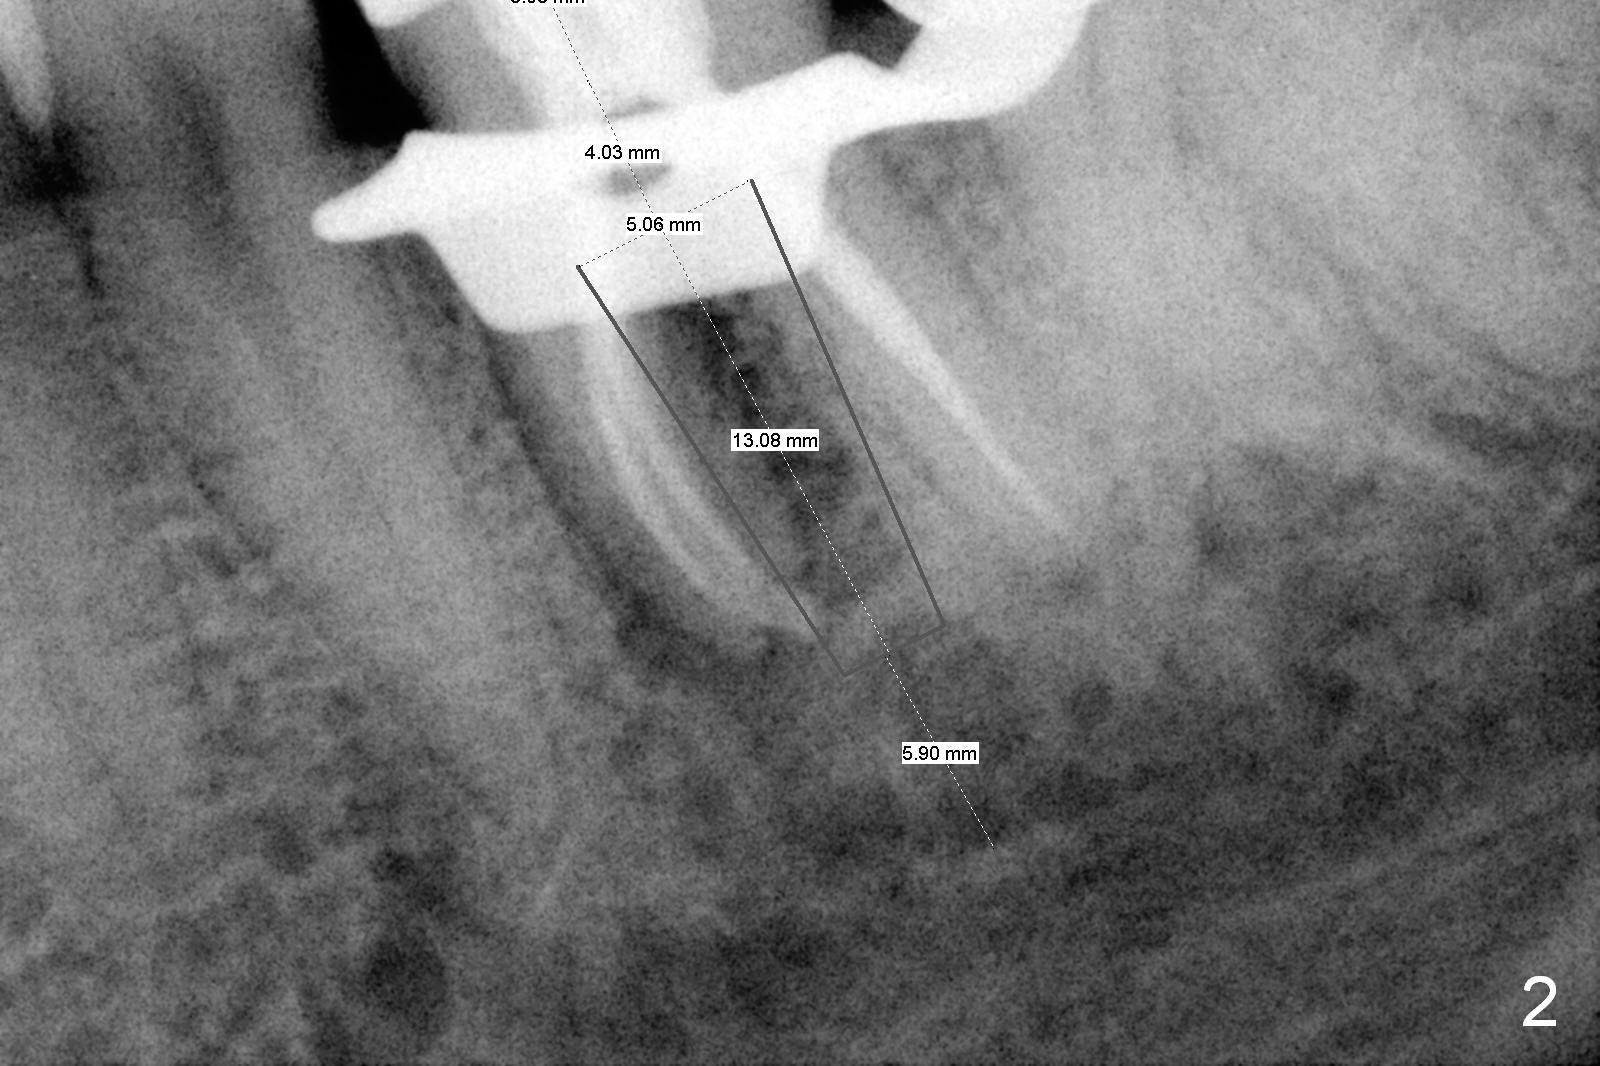

The tooth #19 is easy to get loose, but it cannot be luxated. After sectioning and extraction (Clindamycin), the septum is found to be thin (Fig.4). A surgical fissure bur is used to initiate osteotomy, followed by 1.6 mm pilot drill. It is difficult to use Marking bur (wobbling over the basically pointed septum). It is impossible to use 4.3 mm Magic Drill (MD, one drill system), since it jumps. The smallest MD has to be used (2.8 mm). When the next drill (3.3 mm) is being used for 13 mm with stopper (Fig.5), the patient experiences transient pain. The depth is suggested from the design in Fig.2. The thin septum appears not to be a reliable landmark. When block anesthesia is administered, the initial depth should be shortened. The drill appears to be close to the Inferior Alveolar Canal (Fig.5). Then the depth changes to 11 mm with the following drills (3.8 and 4.3). The mesial and distal walls of the septum are gradually perforated. A 5x9 mm dummy implant is placed only after using 4.8 mm drill (Fig.6). The implant appears to be short. When a longer implant is placed (5x11 mm), it does not easily enter the osteotomy, either sliding into the mesial or distal socket with the implant separating from the implant driver. It appears that a premount implant is appropriate in this situation. When the 5x11 mm implant is finally seated with stability, it is 6 mm apical to the gingival margin. The longest cuff of IBS abutment is 4 mm. A longer implant is needed (Fig.7, 5x13 mm). Placement is not easy as mentioned above. Insertion torque is <20 Ncm when the patient experience a little discomfort. A 6.5x4(4) mm pair abutment is placed (A), apparently proper for restoration. Allograft is placed (Fig.8 *) prior to immediate provisional. The patient complains of bad smell from the site 24 days postop. When the provisional is removed, the abutment is found to be mobile. When the latter is removed with local anesthesia, bone graft granules are attached to the socket above the lightly mobile implant (Fig.9). In fact the latter appears to be stable after a few turns by finger. A healing screw is placed; the socket is closed with collagen plug and 4-0 Chromic gut sutures (Fig.10). It appears that a larger implant should have been used to achieve higher torque. Two months later (3 months postop), the coronal end of the implant is partially exposed. A 5x4 mm healing abutment is placed. It appears that the implant is stable. The implant appears to have osteointegrated 4 months postop (Fig.11). Impression is taken.